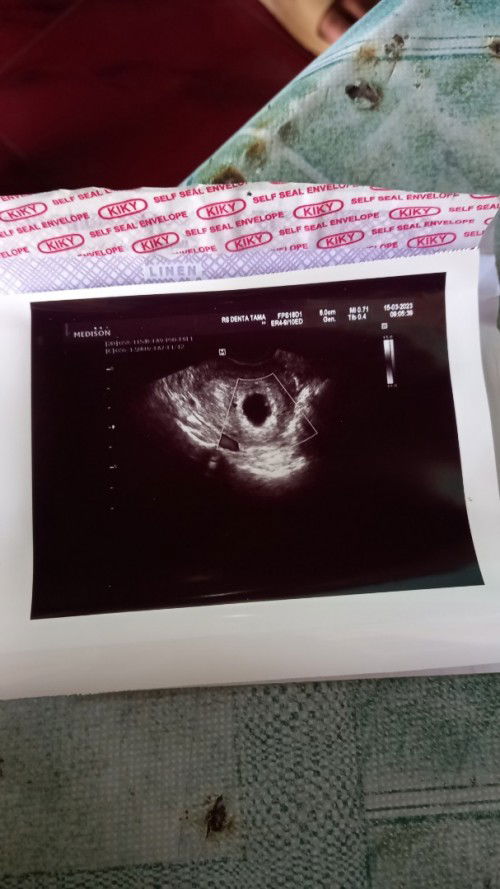

Hamil 7 w,kmrin usg transvaginal bru kantong aja blm ada isinya apa2 ,kira2 msh norml engg y bund,

Hamil 7 week kmrin usg transvag kok bru kntung aja y bun blm ada isinya apa2,apakh msh normal bun